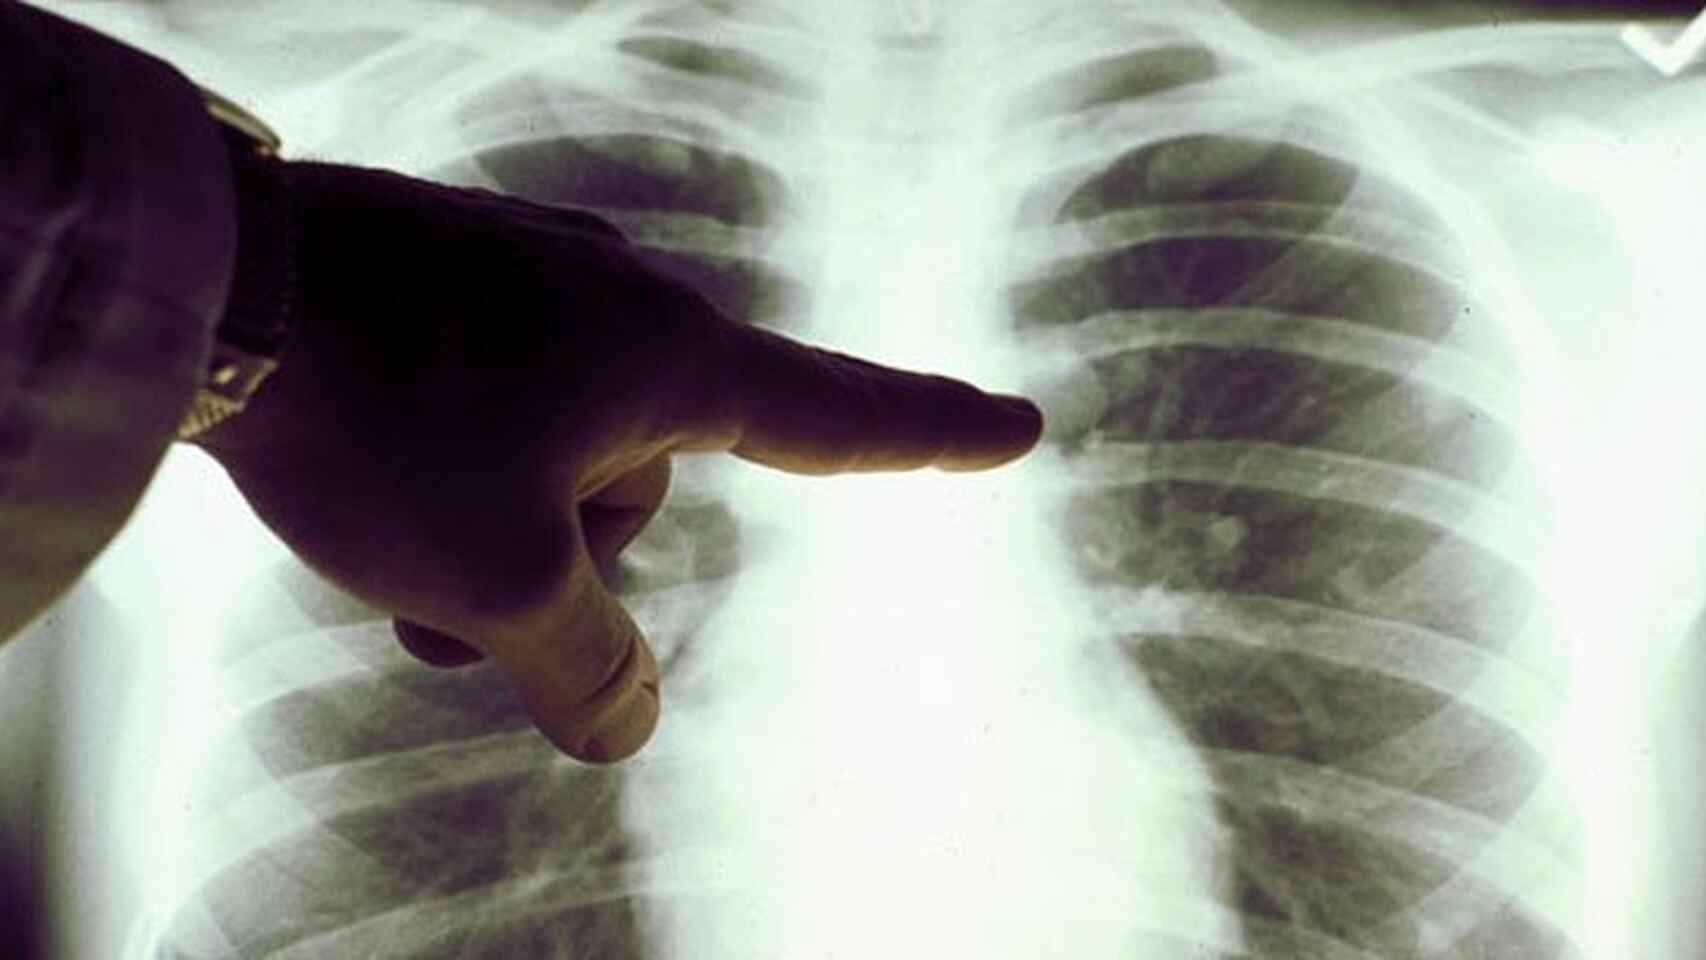

Hay ciertas enfermedades que causan un mayor temor en la sociedad. Este es el caso del cáncer de pulmón. A diferencia de otros padecimientos, este solo causa síntomas cuando ya se ha propagado por gran parte del órgano. Sin embargo, algunas personas con cáncer de pulmón en etapas tempranas presentan síntomas. Por este motivo, en este artículo les contaremos cuáles son los principales síntomas de esta enfermedad. Además, les brindaremos detalles de cómo son los tratamientos y cuál es la esperanza de vida de los pacientes diagnosticados.

Otro de los síntomas más usuales que nos pueden alertar sobre la presencia del cáncer de pulmón es el de desarrollar infecciones como bronquitis y neumonía. Estas no llegan a desaparecer completamente e incluso se convierten en enfermedades crónicas. Además, es necesario prestarle una suma atención cuando uno se enferma rápidamente y la enfermedad ataca directamente al pecho. En estos casos siempre es recomendable recurrir al médico para descartar que sea un posible cáncer de pulmón.